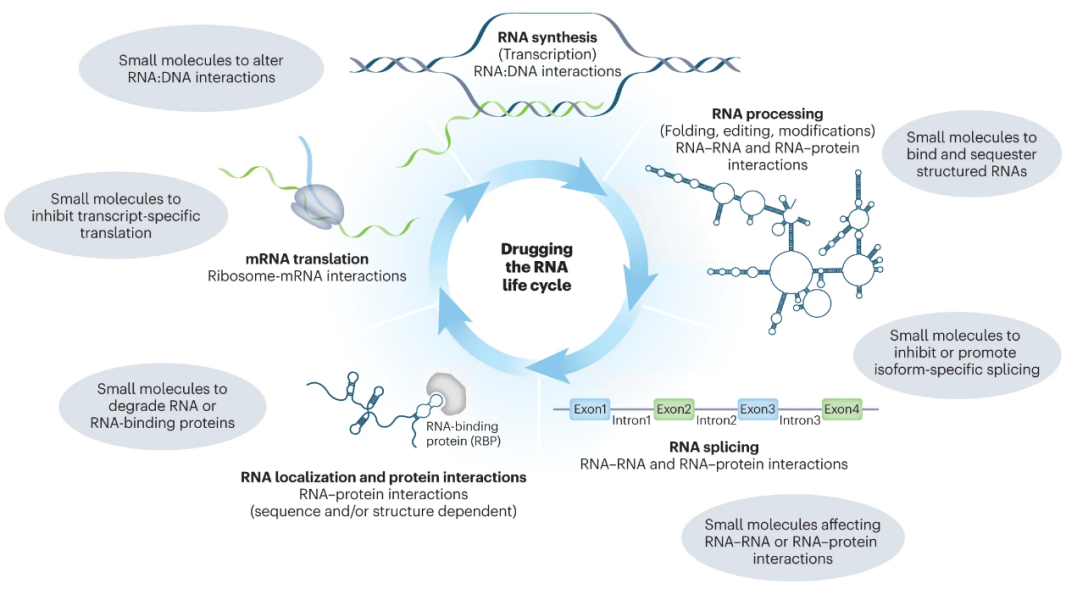

3.靶向RNA的药物研发

针对mRNA的小分子药物具有巨大的治疗潜力,但该领域仍缺乏明确的成功案例。不同公司在这一再兴领域的发展方向存在差异。除生物技术公司外,各制药公司也对靶向RNA小分子方法感兴趣,Merck & Co., Vertex Pharmaceuticals, Sanofi, Amgen, Celgene, Genentech and Janssen Pharmaceuticals都在与该领域的生物技术公司合作。Remix Therapeutics联合创始人兼首席执行官Peter Smith称RNA是“小分子药物发现的下一个前沿”。

RNA的生命周期,图片来源:Xueyi Yang. Image composite by Erin Dewalt